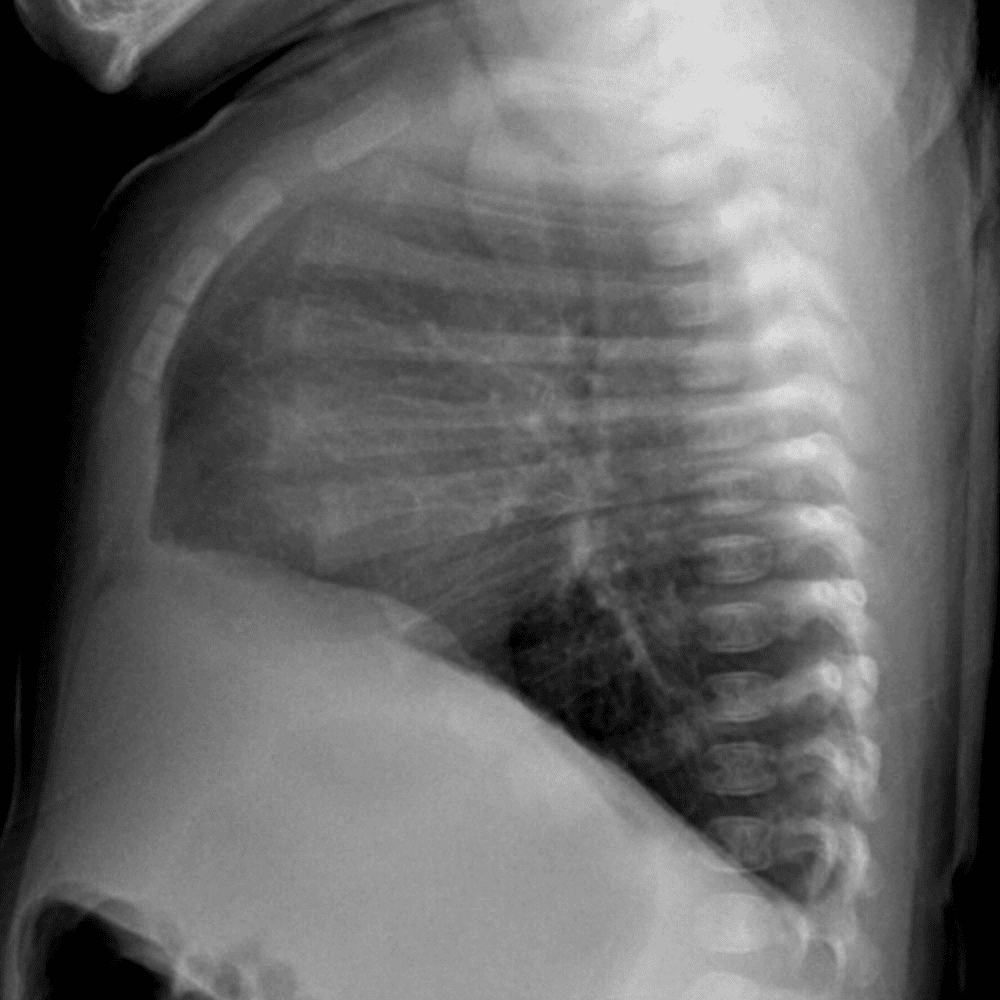

Peds Chest

Practice

Simulates call by including subtle or difficult cases and some normals.

50 cases